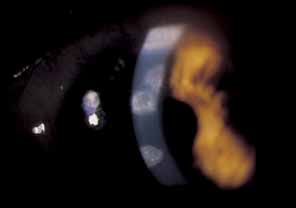

intractable secondary glaucoma, can be observed (Fig. 16). As a result of chronic iridocyclitis, corneal edema secondary to

endothelial damage and sectoral iris atrophy can occur.62 Endothelial cell loss is especially common with herpes zoster keratouveitis, even

with normal intraocular pressure.64,65 Histopathologically, herpes zoster iritis is an ischemic, occlusive vasculitis. The

typical sector iris atrophy that accompanies HZO is the

result of focal ischemic necrosis (Fig. 17).70 In contrast, herpes simplex iritis is primarily a lymphocytic infiltration

without ischemia, and causes a more diffuse iris atrophy.16,72,73  Fig. 16 Herpes zoster ophthalmicus. Corneal edema, abscess formation, and hypopyon

iridocyclitis in an eye that was subsequently enucleated for intractable

glaucoma and pain. Fig. 16 Herpes zoster ophthalmicus. Corneal edema, abscess formation, and hypopyon

iridocyclitis in an eye that was subsequently enucleated for intractable

glaucoma and pain.

|

Fig. 17 Sectoral iris atrophy, status post–herpes zoster ophthalmicus. Note

the moth-eaten appearance of iris in sectoral area, underlying

a corresponding area of sclerokeratitis and limbal vascularization. Fig. 17 Sectoral iris atrophy, status post–herpes zoster ophthalmicus. Note

the moth-eaten appearance of iris in sectoral area, underlying

a corresponding area of sclerokeratitis and limbal vascularization.

|